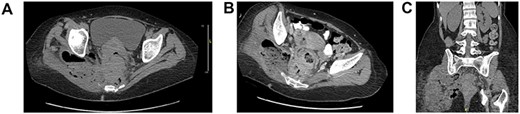

A 50-year-old female with chronic constipation presented to the emergency department complaining of severe right buttock pain, limiting her ambulation for a month, associated with unintentional weight loss of 70 pounds in 3 months. She had no prior colonoscopy. Hemodynamically stable on presentation with right hip tenderness. A CT abdomen and pelvis revealed eccentric rectal wall thickening, pelvic adenopathy, with a presacral abscess of 7.4 × 1.8 × 10.2 cm that appeared to be connected to the right buttock via sciatic notch with the involvement of the right adnexa and uterus as well (Fig. 1). Tumor markers were negative.

Axial (A, B), coronal (C) CT abdomen and pelvis without contrast: complex right adnexal mass containing gas, measuring ~4.5 × 3.5 cm in size. This does appear to be contiguous with small bowel on the right side of the pelvis. Wall thickening of the rectum noted. Perirectal adenopathy, measuring up to 1.4 cm in diameter. There is perirectal soft tissue, which extends to the mesial rectal fascia, posteriorly adjacent to the sacrum and coccyx and to the right side of the pelvis. There are perirectal air collections noted posteriorly. There is a large complex collection which extends through the sciatic notch into the right gluteus muscle, measuring ~9 × 6 cm, containing air and possibly feces. This collection also extends in inferiorly to the level of the ischial spine.